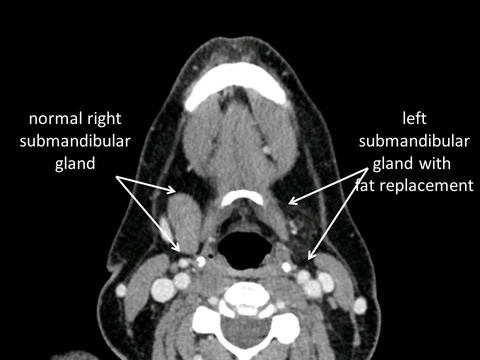

In the absence of bacterial contamination chronic obstruction to outflow of saliva from a major salivary gland often results in its involution as a non-functional asymptomatic remnant of a gland. Although the goal of sialendoscopy-assisted gland-preserving surgery in the management of salivary obstruction from stones and strictures is relief of symptoms and restoration of normal salivary flow, sometimes these dual goals are not achieved. Relief of painful swelling of salivary glands may occur without normal production of saliva when the gland atrophies or involute. Examples of cases are listed below:

44 year old with intermittent swelling of the left submandibular gland for 15 years without treatment to date: